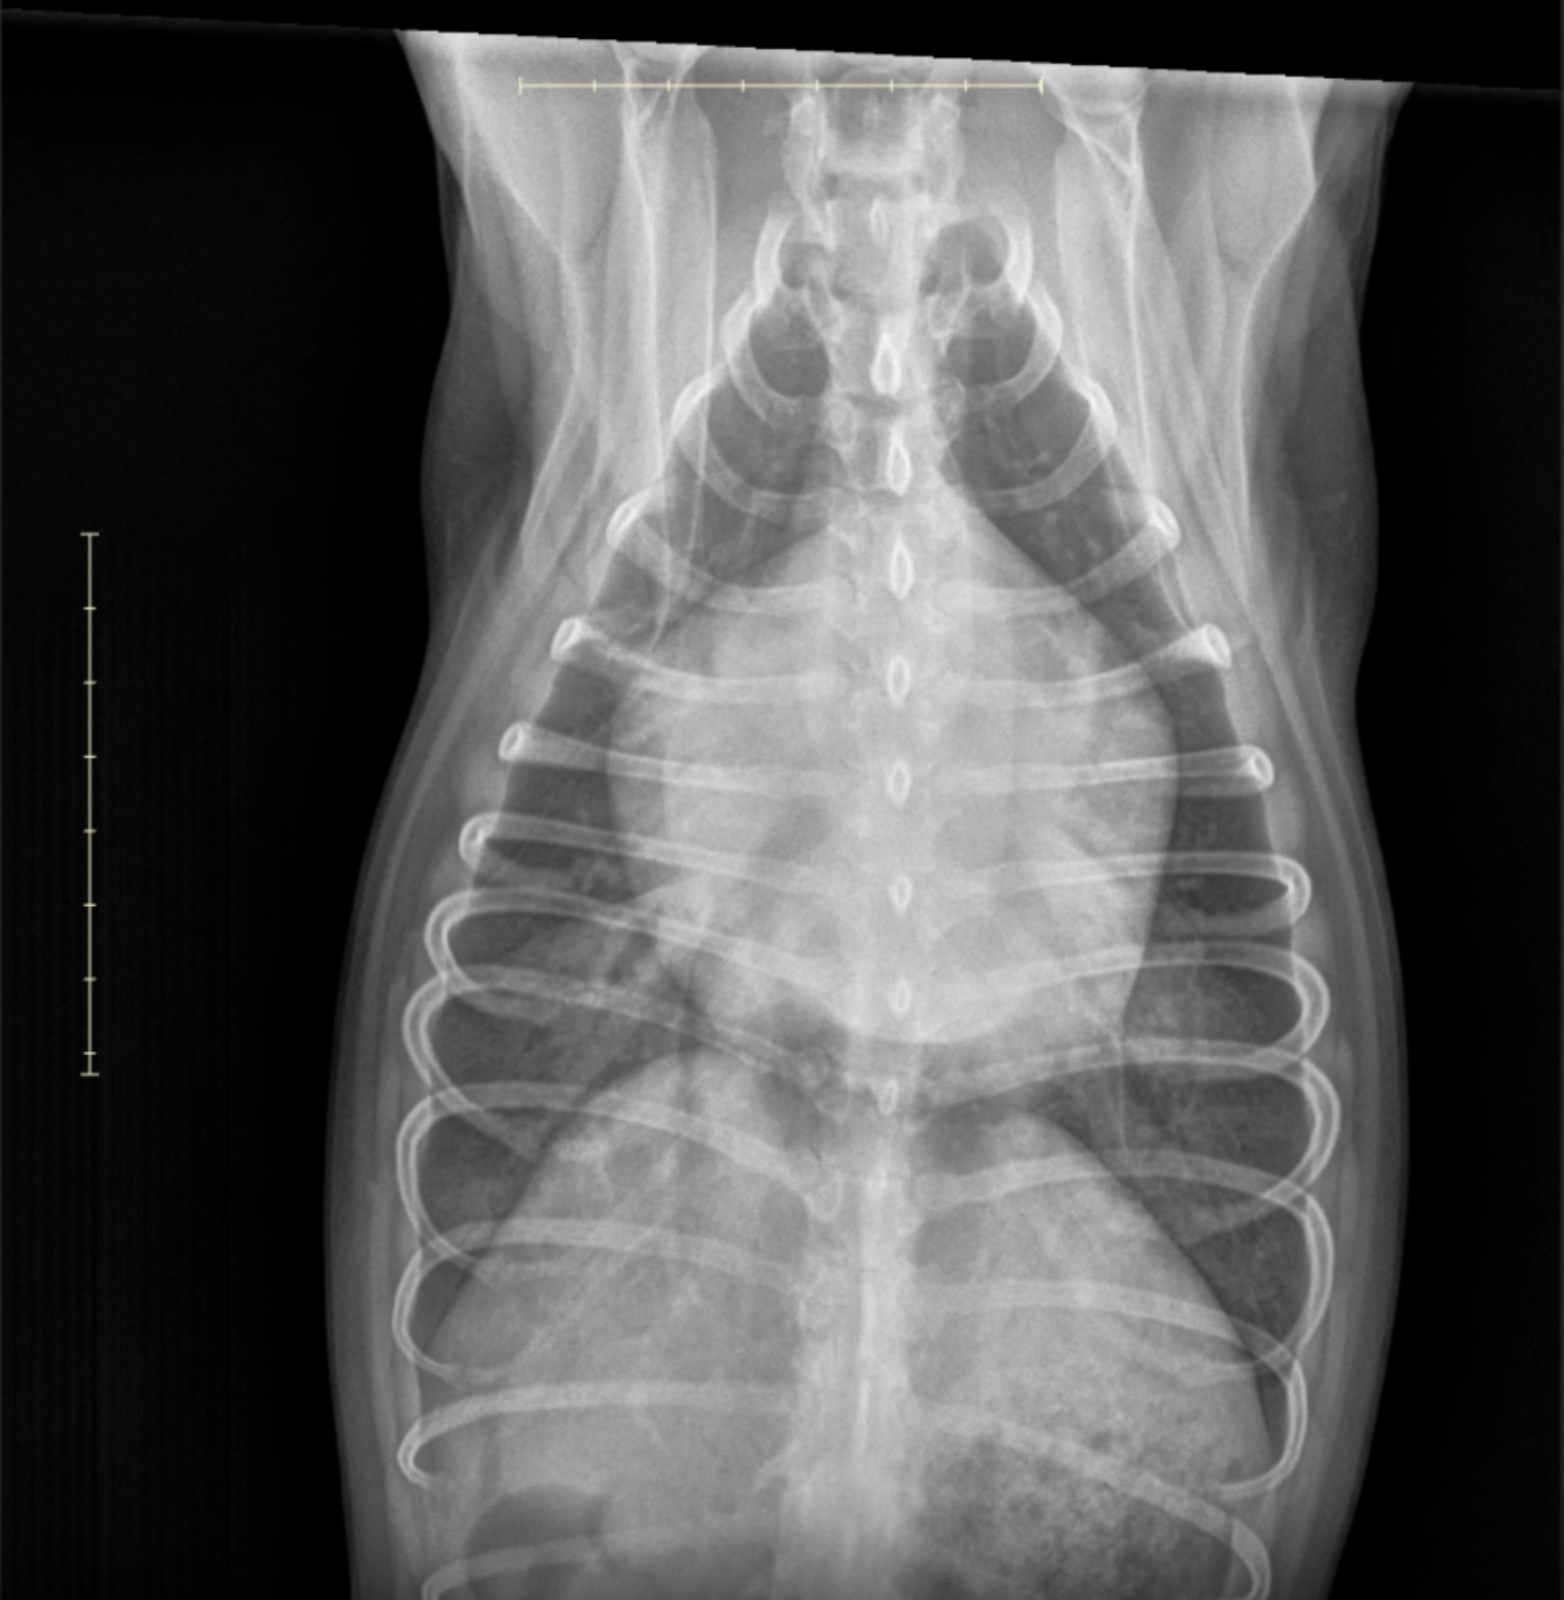

Ventrodorsal thoracic radiograph showing double opacity and bronchial splaying.

Image 2: Ventrodorsal (VD) View

• Cardiac Findings: A clear "double opacity" sign and enlargement of the left atrial silhouette is visible, displacing adjacent bronchi and creating a “bow-legged cowboy” splaying of the mainstem bronchi.

• Pulmonary Pattern: A distinct alveolar pattern is seen, most severe in the perihilar region, consistent with cardiogenic pulmonary edema.

• Vasculature: Pulmonary veins appear mildly distended relative to arteries—supporting a post-capillary (left-sided) cause of congestion.